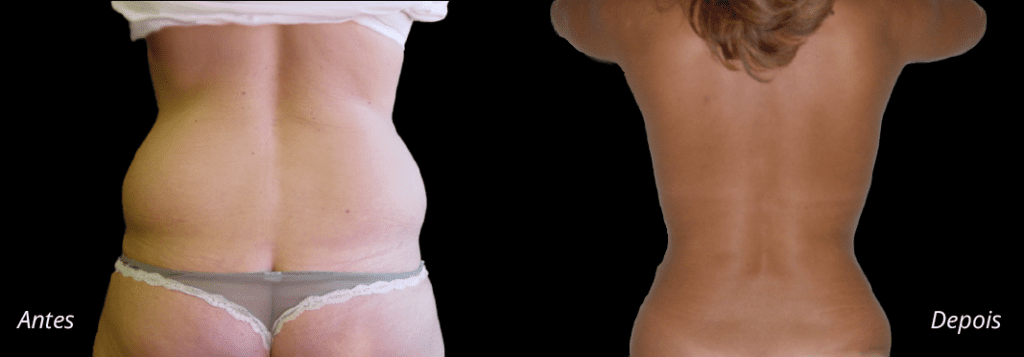

Imagens antes e depois